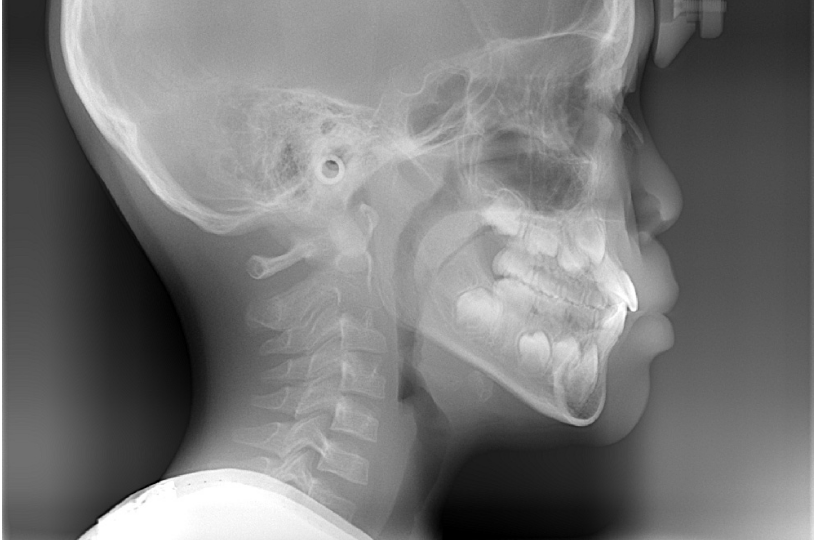

2.検査

レントゲン撮影や口腔内撮影、筋機能の検査などを行います。生え変わりの時期に行う小児矯正では、これから生えてくる永久歯の位置や顎の骨の形・大きさなどを把握することが大切です。当院ではセファロで精密な検査を行うことで、それらの情報を立体的に把握し、治療に取りかかることができます。